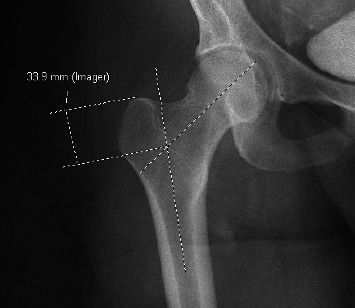

髓内钉固定是股骨骨折手术治疗的“金标准”。虽然钉子设计和患者解剖的许多方面都得到了特别的关注,但股骨近端几何形状的解剖变化和更大的转子高度变化的研究很少。了解大转子与患者人口统计学的潜在关系可能为改善种植体放置提供机会。回顾性审查x线和计算机断层图像的股骨近端进行。纳入标准包括18岁以上具有股骨近端影像学的骨骼成熟患者。纳入标准确定了296例患者。患者平均年龄34±20岁。大转子平均高度为40±8.1 mm。头-柱-骨干平均夹角为141±8.6度。在使用单变量分析确定显著因素后,多变量线性回归显示患者身高和头-柱-骨干角是大转子高度的统计学显著预测因子。患者身高每增加1 cm,大转子高度预计增加0.11 mm (p=0.01)。相反,头柱-骨干角每增加1度,大转子高度相应减少0.17 mm (p < 0.001)。本研究提供的信息可能允许潜在的优化种植体设计或种植体位置,以减少近端钉突出,增强钉配合,并根据所使用的种植体近端钉尺寸确保头髓延迟螺钉在头部的位置。

Intramedullary nail fixation is the "gold standard" for surgical intervention of femoral fractures. While many aspects of nail design and patient anatomy have received specific focus, anatomic variations in proximal femoral geometry and greater trochanteric height variation have been poorly studied. Understanding the potential relationship of the greater trochanter to patient demographics may provide an opportunity to improve implant placement. Retrospective review of x-ray and computed tomography images of the proximal femur was performed. Inclusion criteria consisted of skeletally mature patients over 18 years old with imaging of the proximal femur. Inclusion criteria identified 296 patients. Mean age of included patients was 34 ± 20 years. Average greater trochanter height was 40 ± 8.1 mm. Mean caput-collum-diaphyseal angle was 141 ± 8.6 degrees. After identifying significant factors using univariate analyses a multivariable linear regression demonstrated that patient height and caput-collum-diaphyseal angle were statistically significant predictors for greater trochanter height. For every 1 cm increase in patient height there was a predicted 0.11 mm increase in greater trochanter height (p=0.01). Conversely, every 1 degree increase in caput-collum-diaphyseal angle results in an associated 0.17 mm decrease in greater trochanter height (p < 0.001). This study provides information that may allow for the potential optimization of implant design or implant position to minimize proximal nail protrusion, enhance nail fit and ensure cephalomedullary lag screw position in the head based on the proximal nail dimensions of the implant used.